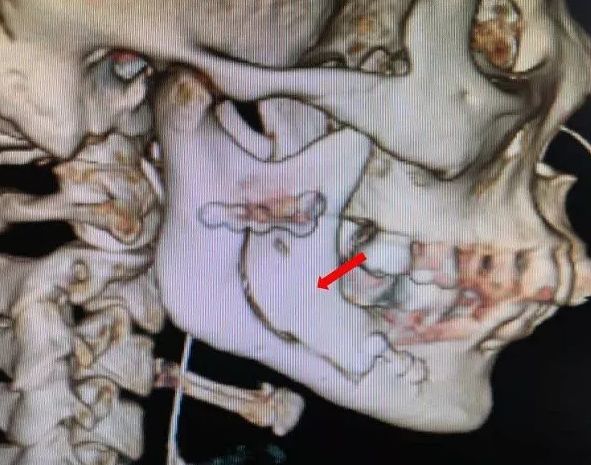

可就在上周,牙疼的程度已经进展到让小莫难以忍受。在家人的陪同下,他来到了杭州市第一人民医院。本以为是简单的牙痛,可令所有人没想到,颌骨3D-CT显示,颌骨被病变“吃掉”了二分之一,里面空了一个“大窟窿”,也就是说,右侧下颌骨体连同整个升支部存在大范围的骨质破坏。

影像检查发现一侧颌骨被肿瘤侵蚀

2.成釉细胞瘤X线表现特点是:早期呈蜂窝状,以后形成多房性囊肿样阴影,单房较少,囊壁边缘不整齐,有半月形切迹,囊内牙根有不规则吸收现象。